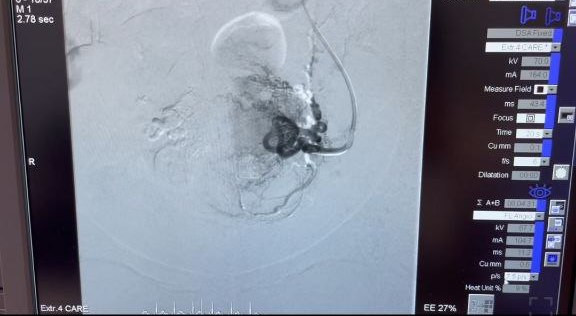

На базе АНО «Центральная клиническая медико-санитарная часть» прошёл обучающий курс и мастер-класс «Эмболизация маточных артерий с применением микросфер «Сфера-Спектр». Магнитогорские врачи поделились своим опытом с коллегами из Челябинска и Троицка.

Первую операцию по эмболизации маточных артерий в медсанчасти провели в декабре 2000 года. Тогда врачи отделений гинекологии и ангиографии АНО «ЦКМСЧ» стали одними из первых в России, кто освоил эту методику лечения миомы матки.

Эмболизация маточных артерий – это малоинвазивный и органосохраняющий метод лечения миомы матки и некоторых видов кровотечения. С его помощью можно не только устранить симптомы заболевания и прекратить рост миоматозных узлов, но и сохранить главное – репродуктивную функцию женщины. Эта методика не требует открытого хирургического вмешательства, а потому реабилитация пациенток проходит значительно быстрее.

Обучающий курс включал в себя как теоретическую, так и практическую части. Гинекологи и врачи по рентгенэндоваскулярным диагностике и лечению из Челябинска и Троицка смогли наблюдать за работой опытных магнитогорских коллег в операционной.

Медсанчасть входит в пятёрку медицинских учреждений в стране по количеству проведённых операций по эмболизации маточных артерий. В прошлом году врачи АНО «ЦКМСЧ» провели более 250 таких операций.